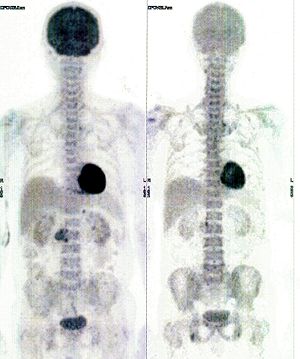

Below are some of the cases, from more than 80 cases we have treated so far with good results. When reading the PET/CT scans, the picture on the left is before treatment, and the picture on the right is after treatment. The intensity of black represents the activity of the cancer, but some black areas are not cancer: brain, heart, radioactive urine in bladder. For the heart, the intensity of black depends on the number of hours of fasting: if more than 10 hours, the heart is not even black, but if fasting is less than 6 hours, it is very black. The intensity of black in the brain can be variable in different scans depending on the brain activity at the time of the scan. The intensity of black in the radioactive urine can also be variable due to the hydration of patients and the time of injection of diuretic.

CASE NO: 2 (HEPATOCELLULAR CARCINOMA)

A 40+ man with hepatocellular carcinoma, an incurable cancer. After 2 treatment, the activity of the hepatocellular carcinoma is less.

CASE NO: 2 (HEPATOCELLULAR CARCINOMA) - After a few more treatments

After another few treatment, the activity of the hepatocellular carcinoma is much less. The patient never came back for further treatment, but this case, and case no: 1, shows that incurable hepatocellular carcinoma, often seen in hepatitis B and C patients, can be cured.